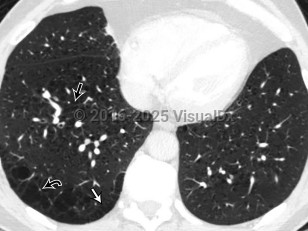

Allergic bronchopulmonary aspergillosis

Extrinsic allergic alveolitisExtrinsic allergic alveolitis